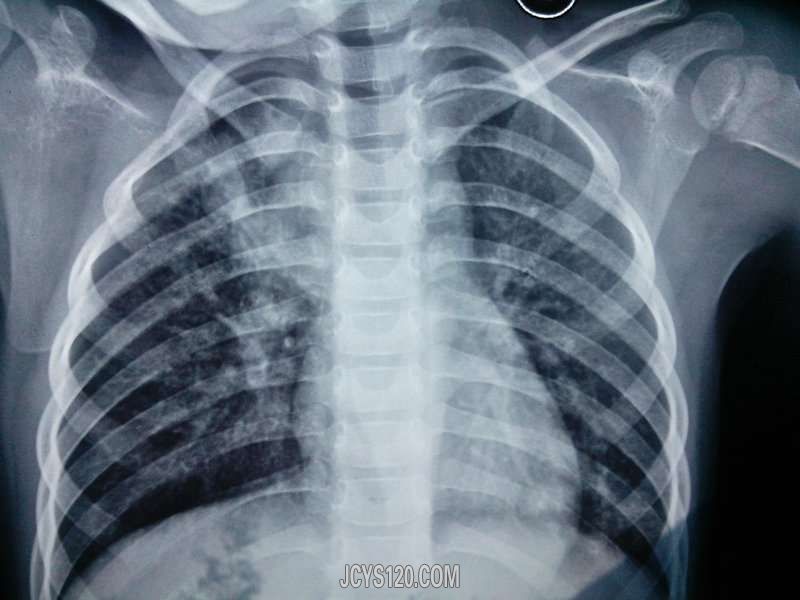

2小时前发热就诊,体温在家自测39°c,来诊后查体咽红充血,双肺呼吸音粗,未闻及干湿罗音,因为患儿服药困难所以给予输液治疗,头孢他啶、炎唬宁、利巴韦林三组液体,口服萘普生退热,液体用完,热退,第二天复诊,述回家后半夜体温再次升高到39°c,口服退烧药后下降至正常,考虑感冒,病程所致,没有调整方案,继续治疗,期间查体未发现有较前加重的症状,第五天为了明确诊断,建议患儿去医院检查,结果回报吓了一跳,右上肺炎(具体见胸片),调整治疗方案,给予青霉素、痰热清静滴5天,阿奇霉素5天,期间体温还是一直反复,建议患者住院治疗,住院后给予阿奇霉素(连续使用5天停三天,再用5天)头孢西丁等药物治疗,总时间24天才得以痊愈。第一次遇到病程这么长的,自认为期间的抗生素、激素的使用还算合理及时,不过真是想不通为什么会这样?无独有偶,接下来的一段时间连续遇到好几例,症状都差不多,因为前面的经验,发热两天后稍有咳嗽的,就建议胸片检查,还真查出好几例肺炎患儿。。。大家有遇到的吗?病程如此之长为何? [align=center] [/align]